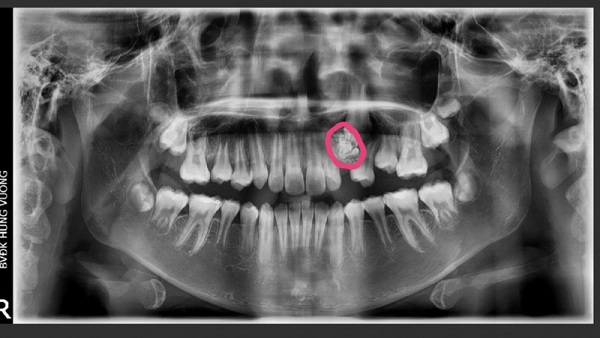

Trước đó, trường hợp này đến bệnh viện khám vì răng nanh hàm trên bên trái vẫn chưa mọc dù bệnh nhân đã 12 tuổi. Phim chụp X-quang răng toàn cảnh thể hiện hình ảnh khối u răng kết hợp tại vị trí hàm trên bên trái.

Khối u răng qua hình ảnh X - quang răng toàn cảnh.

Bệnh u răng rất khó để phát hiện do khối u không gây đau nhức, chỉ qua phim chụp X-quang răng toàn cảnh (Panorama toàn hàm) mới có thể nhìn thấy. Phương pháp điều trị duy nhất là phẫu thuật để lấy u. Nếu được phát hiện sớm phẫu thuật sẽ đơn giản. Trường hợp chậm trễ sẽ rất khó điều trị, thậm chí để lại nhiều di chứng gây nguy hiểm đến tính mạng.